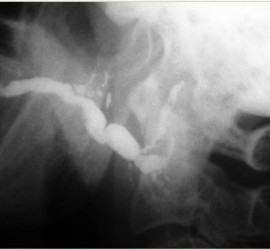

Аденокарцинома — злокачественные эпителиальные опухоли, образующие железистые и папиллярные структуры, но не имеющие характерных признаков других видов рака слюнных желез. Возникают как в больших, так и в малых слюнных железах. Гистологически связаны с протоками слюнных желез. Наиболее характерные морфологические признаки аденокарциномы слюнных желез — пролиферация эпителия в протоковых образованиях в виде […]